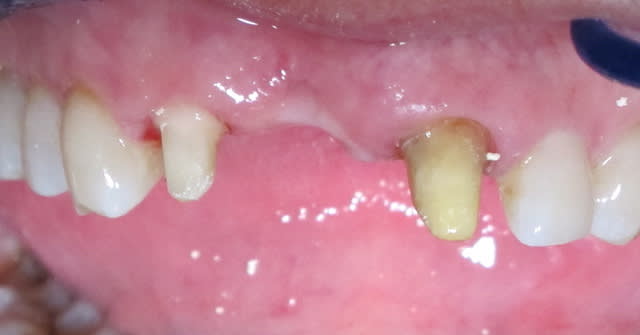

Img 5815 gymgib - Eugenol

Img 5816 okgijh - Eugenol

j'aurais bien aimé voir le défaut osseux/gingival dessous...

parce que quitte à faire le bridge, un bon steak de conjonctif enfouis pour redonner du volume au niveau de la dent absente, un bridge prov pendant la phase de cicat avec un ovate pontique et amha plus besoin de cette fausse gencive...

L'état paro du bas est super moche.

Pas emballé. L'esthétique est certes sympathique, mais il sera absolument impossible pour le patient d'assurer une hygiène correcte là-dessous. Paro à prévoir de manière rapide...

Pour ce qui est du cas, je trouve aussi que l'implant est beaucoup plus indiqué. Ce cas est un cas "complexe" si on veut le réhabiliter par technique fixe sur moignon dentaire ( diastème, hauteur des dents, forme du pontic....). Pour moi ce cas c'est soit implant soit restauration fixée conventionelle de l'ensemble du secteur incisivo canin avec chirurgie parodontale pour rendre la forme des dents plus harmonieuses et eviter la fausse gencive....autant te dire qu'avec tout le HN ( elongations coronaire et couronnes sur dents vitales) l'implant revient moins cher